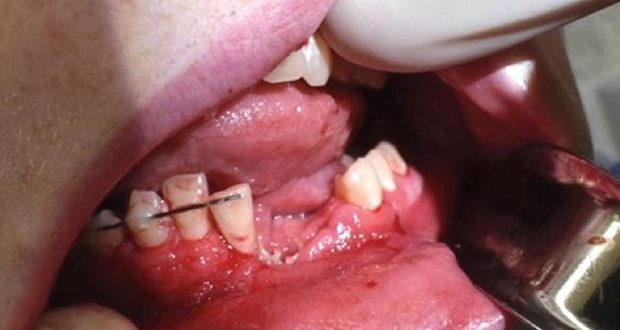

Los médicos tuvieron que extraerle al adolescente varios dientes incisivos después de que sus encías resultaran destruidas, explicó al portal Live Science la cirujana Katie Russell, quien atendió al afectado en la sala de emergencias de un hospital de la ciudad de Salt Lake City.

Para estabilizar su hueso mandibular, los facultativos le colocaron un arco de ortodoncia debajo de las encías inferiores, pero pese a ello la boca no se cerraba de manera correcta, por lo que decidieron mantenerle la mandíbula cerrada durante seis semanas fijándola con alambres para evitar cualquier movimiento que pudiera comprometer la recuperación.